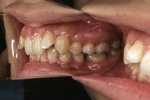

矯正の症例

| 【Before】 | 【After】 | |